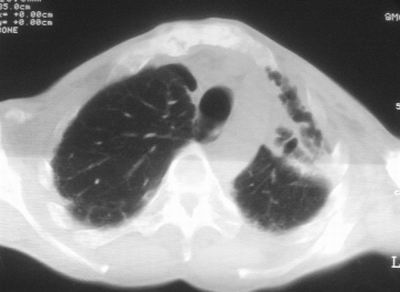

标题: CT11864:男,47岁,反复咳嗽、咯痰、咯血3年,请分析. [打印本页]

患者,男,47岁,反复咳嗽、咯痰、咯血3年,再发5天。痰培养未找到真菌、抗酸杆菌、癌细胞。

左肺上叶体积明显缩小,其内见多发透光区,纵隔向左侧移位,左肺下叶多发班片状病灶,边界模糊,1左肺上叶先天肺发育不全,2左肺下叶肺炎,

左肺上叶结核伴肺纤维化,纵隔移位,左肺下叶感染性病变,建议抗炎抗结核后复查,双肺气肿.

以下是引用xulianj在2008-2-25 21:01:00的发言:[br]左肺上叶结核伴肺纤维化有霉菌球形成,纵隔移位,左肺下叶感染性病变,建议抗炎抗结核后复查,双肺气肿.

考虑:左肺慢纤伴霉菌球形成、双肺全小叶型肺气肿。

1)考虑为:左肺上叶肺结核(空洞形成),伴左下肺感染;不排除霉菌感染可能。2)肺气肿。

左肺上叶结核伴肺纤维化空洞形成并左肺下叶感染,纵隔牵拉移位,建议作进一步检查排除左侧肺霉菌感染可能。